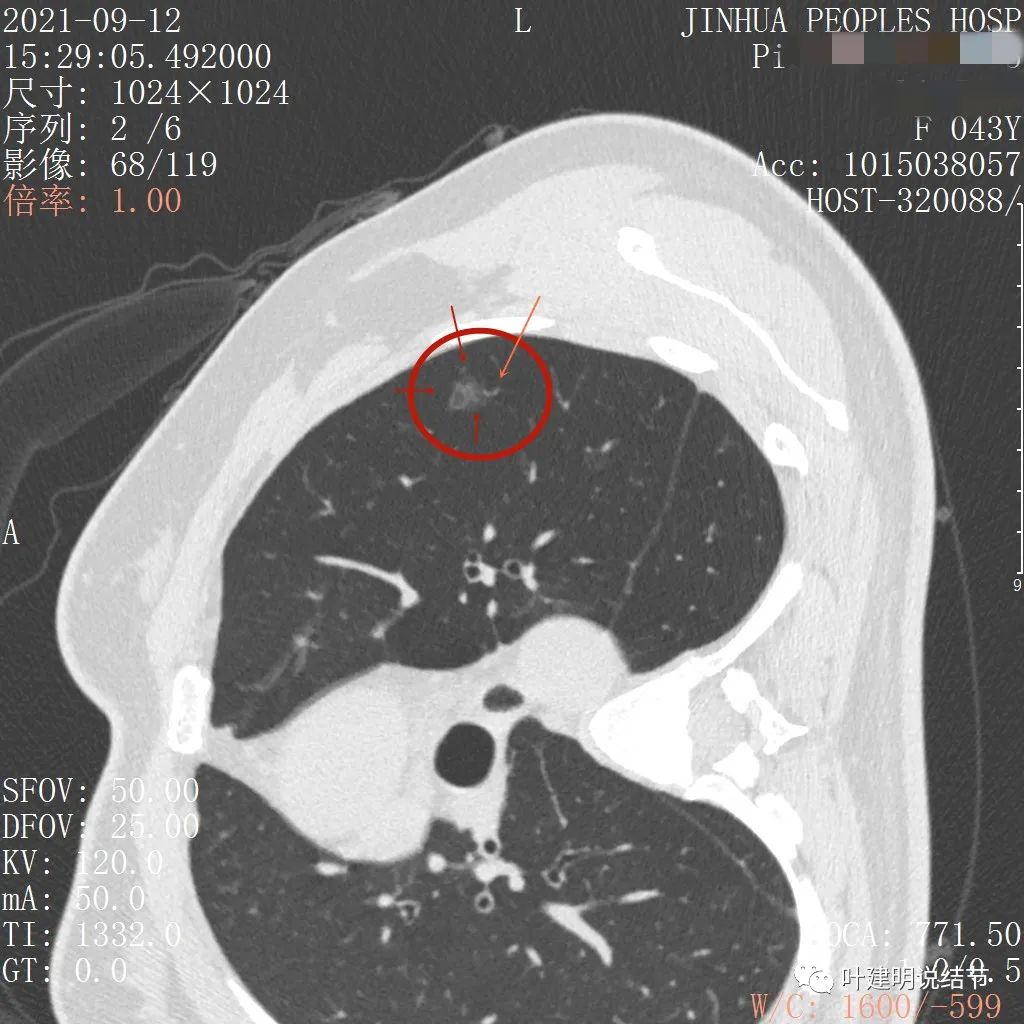

上图示病灶内部有高密度点状成分(粉色箭头所指)

同样示内部点状高密度,瘤肺边界清,密度显乱

上图显示混合磨玻璃结节,中间点状高密度区域,边上有微小血管征